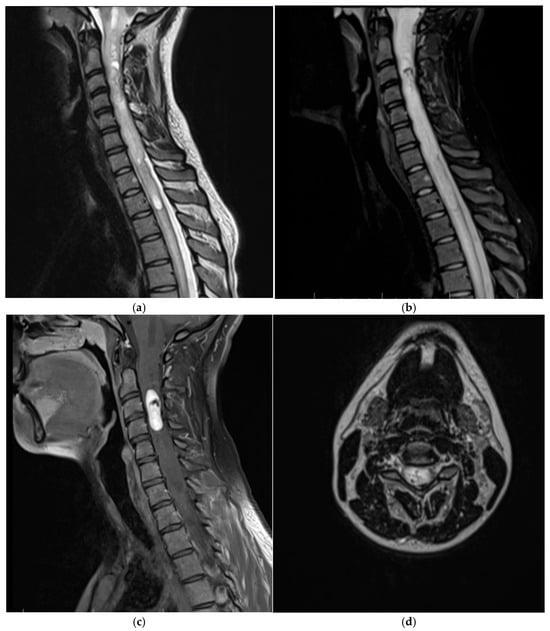

3.1.2. Patient Two

| Our case (Patient 2) | 24/F | Cervical, intramedullary | 3 cm | yes | S100 | GFAP SOX10 CD24 EMA CKAE1/3 PR |